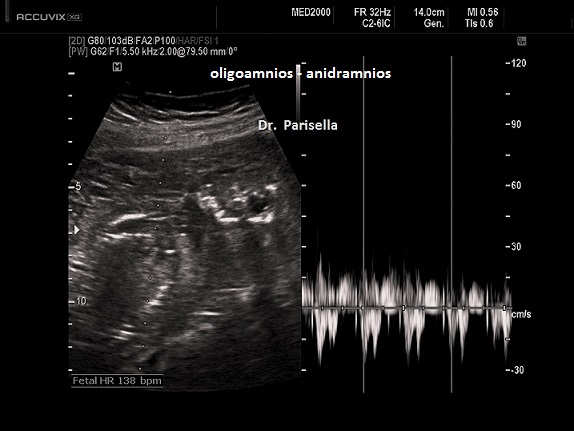

- il tipo I caratterizzata da placentomegalia ad aspetto multicistico, normosviluppo fetale e set cromosomico aggiunto di origine paterna (la dispermia è la causa più frequente di triploidia), micrognazia, anomalie del SNC (idrocefalia), cardiopatie, igroma cistico, oligoamnios.

- il tipo II caratterizzata da una placenta piccola, IUGR, set cromosomico aggiunto di origine materna (diginia), micrognazia, anomalie del SNC (idrocefalia), cardiopatie, igroma cistico, oligoamnios.